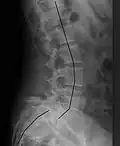

Radiografía de una anterolistesis de grado 4 en L5-S1 con desalineación espinal indicada

-